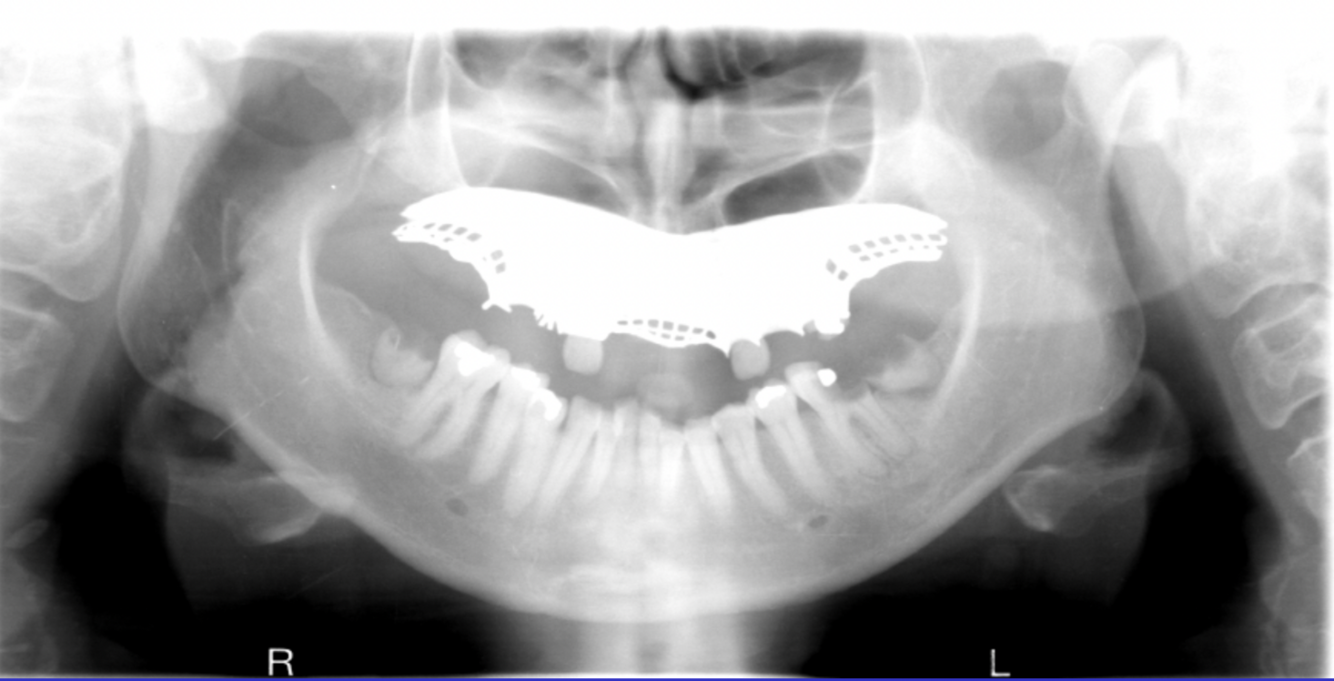

What are the errors in this radiograph? What is the cause of these errors?

A

1. anterior teeth widened and blurred

2. inferior tubercles and meati spread across maxillary sinuses

3. condyles close to or cut off side of image

cause: patient too far back